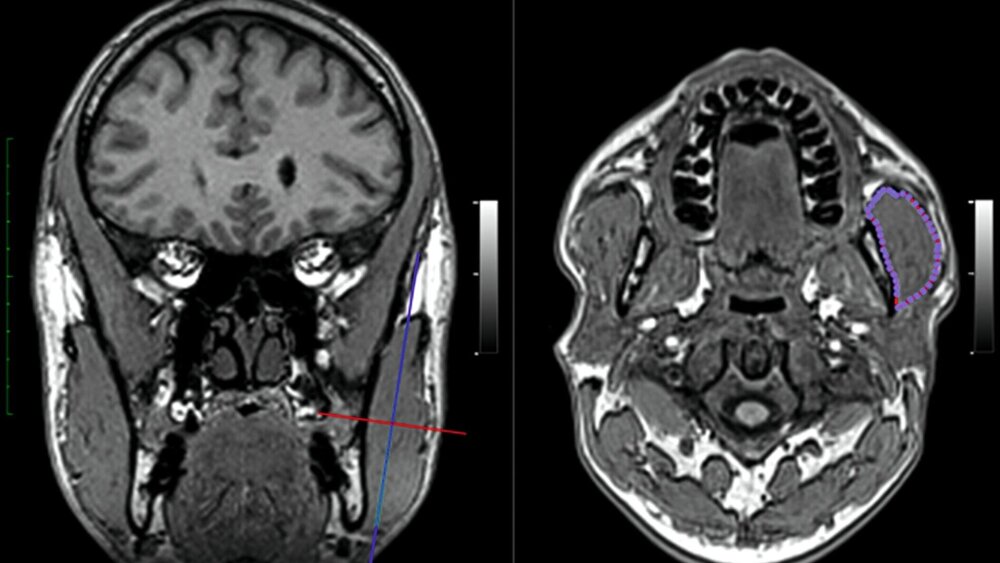

Die Greifswalder Arbeitsgruppe wollte herausfinden, ob es geschlechtsspezifische Unterschiede in der Ausbildung des Musculus masseter im Hinblick auf das Vorhandensein von Bruxismus gibt. Dazu maßen sie bei insgesamt 720 Probanden im Alter von 30 bis 89 Jahren (391 Frauen und 329 Männer) die Querschnittsfläche des Musculus masseter. Die Probanden wurden aus dem Teilnehmerpool der Study of Health in Pomerania (SHIP) rekrutiert, einer bevölkerungsbasierten Querschnittsstudie zur Untersuchung der Prävalenz und Inzidenz häufiger bevölkerungsrelevanter Krankheiten und ihrer Risikofaktoren in Nordostdeutschland. Dabei unterzogen sich die Teilnehmer einer MRT-Bildgebung und einer oralen Untersuchung. Die Querschnittsflächen der Massetermuskeln auf beiden Seiten wurden anhand von MRT-Bildern vermessen. Parafunktionelle Aktivitäten wie Knirschen und/oder Pressen im Schlaf- oder Wachzustand wurden aus dem zahnärztlichen Interview ermittelt.

Die Auswertung der Messwerte zeigte, dass eine größere Masseterdicke mit der Häufigkeit des Bruxismus bei Männern assoziiert war, aber nicht bei Frauen. Die größere Masseterdicke bei knirschenden Männern manifestierte sich vor allem bei starken Bruxern, nicht aber bei der Gruppe, die weniger häufig knirschte. Obwohl Frauen häufiger an Bruxismus litten, war der Querschnitt des Massetermuskels bei bruxierenden Männern signifikant höher, während bei Frauen fast keine Größenunterschiede in Bezug auf Bruxismus festgestellt wurden. Diese geschlechtsspezifischen Unterschiede im Querschnitt des Musculus masseter waren im Hinblick auf den Mittelwert signifikant groß.